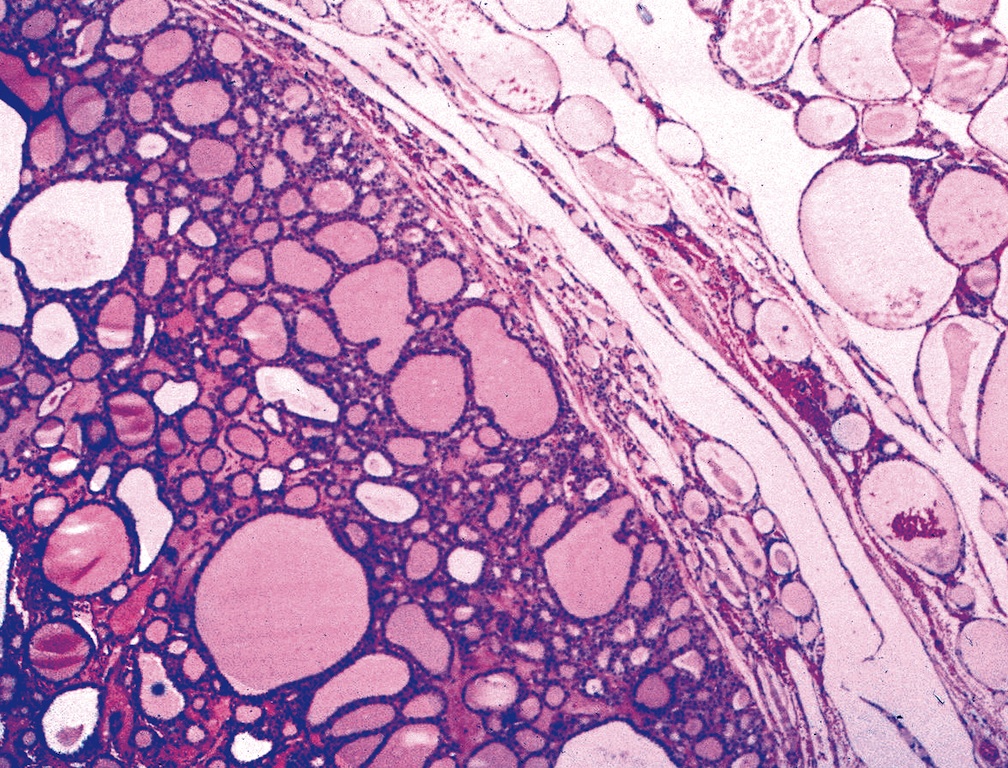

Follicular Adenoma of Thyroid Gland Stock Image Image of endocrine

Follicular adenoma of thyroid gland, light micrograph. Histopathology Differentials Of Thyroid Adenoma Differential gene expression can help in differential diagnosis between follicular adenoma and follicular thyroid carcinoma (int j. On ultrasound, an adenoma appears as a solid mass in contrast to a thyroid cyst. A thyroid adenoma is a noncancerous lesion on the thyroid. Although they’re not cancer, they can still affect your overall health. A thyroid nodule is a discrete lesion. Differentials Of Thyroid Adenoma.